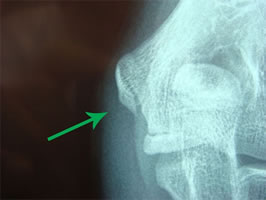

今回の患者様にも専門整形外科での検査などを依頼し、実施して頂きました。以下の写真(↓)は、左右の肘関節レントゲン画像です。矢印の先が剥離骨折部です。

患側の右肘拡大です。

赤色矢印の先に、横向きに黒い線が確認できますでしょうか。

次に健側の左肘拡大です。

緑矢印の先には、患側と異なり、横方向の黒い線がありません。